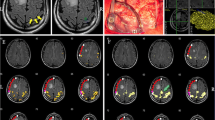

After the images were co-registered in the neuronagivation system using ‘point merge’ and ‘surface merge’, the results of fMRI and ECS were compared for each patient separately. Sites with ECS-related motor responses were highlighted with sterile markers and registered by the neuronavigation system just before starting the tumour resection (Fig. 1). The distance between the marker representing the hand M1 cortex and the nearest border of the BOLD signal cluster as part of the SM1 cortex was measured using a sterile surgical ruler. The volumes of the tumour and BOLD signal clusters were then calculated using the Treon device software after manual delineation of the borders in each axial plane.

Excellent concordance between fMRI and ECS results in localizing primary hand motor cortex in patient (No.14) with oligodendroglioma (grade II). A, B, C—coronal, sagital, axial projection of the primary hand motor cortex according to ECS covered by BOLD activation as displayed during intraoperative neuronavigation D—intraoperative photograph; asterix = expected primary hand motor cortex according to fMRI; label Δ1 = area of motor response to ECS; TU and blue line = border between tumour and primary motor cortex I—BOLD activated areas (P < 0.05 FWE corrected) elicited by left hand tapping task II—postoperative T2-weighted MRI

Comparison of the fMRI and ECS results

In twelve patients the results of both methods were in a full agreement, i.e., the motor response was successfully elicited from areas with significantly increased BOLD signal in the M1 cortical area. This was observed in seven patients evaluated conservatively at the P < 0.05 level with FWE correction (Fig. 1). In three patients (two of them at P < 0.05 corrected and in one patient at P < 0.001 uncorrected level) the agreement between the two methods was only partial with one positive motor response elicited from the cortex out of the BOLD signal cluster, albeit within the same gyrus.

BOLD signal suppression by collateral oedema also applied to a 50-year-old patient (No. 11) with a glioblastoma. According to fMRI (P < 0.001 uncorrected), the M1 was expected 25 mm in front of the tumour (Fig. 2) when it was actually located only 5 mm anteriorly as documented by ECS.

An example of insufficient concordance between fMRI nad ECS in patient (No.11) with glioblastoma multiforme. A, B—coronal and sagital projection of primary hand motor cortex according to fMRI C—intraoperative photograph demonstrating lack of fMRI / ECS concordance (the same labelling as in Fig. 1) I—BOLD activated areas (P < 0.001 uncorrected) elicited by repetitive left hand grasping II—sagital postoperative contrast T1-weighted MRI III—axial postoperative T2-weighted MRI